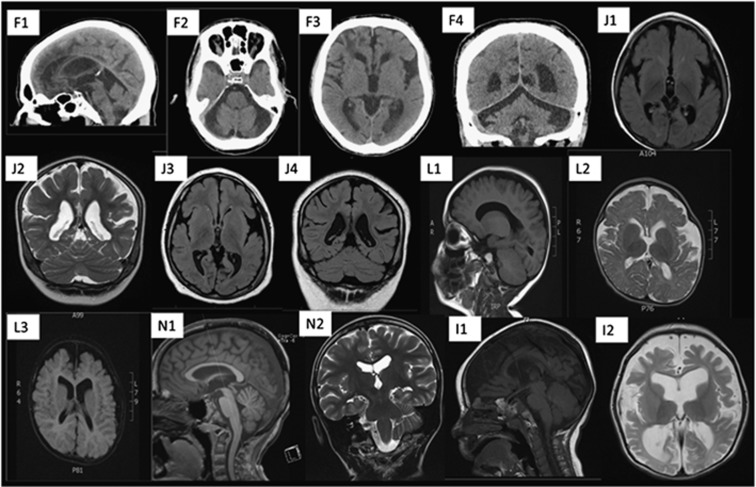

Variants in CLCN4, which encodes the chloride/hydrogen ion exchanger CIC-4 prominently expressed in brain, were recently described to cause X-linked intellectual disability and epilepsy. We present detailed phenotypic information on 52 individuals from 16 families with CLCN4-related disorder: 5 affected females and 2 affected males with a de novo variant in CLCN4 (6 individuals previously unreported) and 27 affected males, 3 affected females and 15 asymptomatic female carriers from 9 families with inherited CLCN4 variants (4 families previously unreported). Intellectual disability ranged from borderline to profound. Behavioral and psychiatric disorders were common in both child- and adulthood, and included autistic features, mood disorders, obsessive-compulsive behaviors and hetero- and autoaggression. Epilepsy was common, with severity ranging from epileptic encephalopathy to well-controlled seizures. Several affected individuals showed white matter changes on cerebral neuroimaging and progressive neurological symptoms, including movement disorders and spasticity. Heterozygous females can be as severely affected as males. The variability of symptoms in females is not correlated with the X inactivation pattern studied in their blood. The mutation spectrum includes frameshift, missense and splice site variants and one single-exon deletion. All missense variants were predicted to affect CLCN4's function based on in silico tools and either segregated with the phenotype in the family or were de novo. Pathogenicity of all previously unreported missense variants was further supported by electrophysiological studies in Xenopus laevis oocytes. We compare CLCN4-related disorder with conditions related to dysfunction of other members of the CLC family.